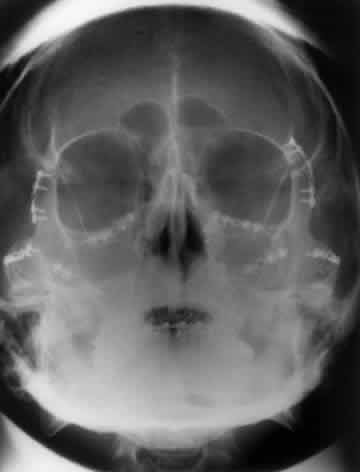

In an attempt to improve the visualization of the maxillary and ethmoid sinuses, in 1915 Waters and Waldron7 described a radiographic projection (Fig. 2) that eliminated the overlapping shadows of the dense petrous ridge of the temporal bone. Waters projection is created by placing the chin of the patient on the x-ray cassette with the canthomeatal line (the line that connects the lateral canthus and the external auditory meatus) at 37 degrees to 45 degrees.5,6 This orientation is accomplished if the nose of the patient is approximately 0.5 to 1.5 cm above the x-ray plate.7,8 A mnemonic is—the patient raises the chin up to sip water.

Fig. 2. A. Schematic showing positioning for a Waters projection. (CM, canthomeatal line; CR, central ray) B. Radiograph of a Waters projection. The petrous ridge lies below the maxillary sinus. (a, frontal sinus; b, medial orbital wall; c, innominate line; d, inferior orbital rim; e, orbital floor; f, maxillary antrum; g, superior orbital fissure; h, zygomatic-frontal suture; i, zygomatic arch) (A; Rao VM, Gonzalez CF: Plain film radiography and polytomography of the orbit. In Gonzalez CF, Becker MH, Flanagan JC [eds]: Diagnostic Imaging in Ophthalmology, pp 1–7. New York, Springer Verlag, 1986)

Waters view provides the best image of the maxillary antrum and good images of the orbital rim, orbital floor, zygomatic bones and arches, lesser wing of the sphenoid, and infraorbital foramen. This view is useful to the clinician in orbital floor fracture assessment because of the clear image of the orbital floor and the underlying maxillary sinus. The floor of the orbit should form a continuous radiographic line with the lateral wall of the orbit. Confusion can occur regarding the location of the orbital floor and its relationship to the orbital rim. The orbital floor is located inferior to the orbital rim not in the same plane, because of the orientation of the patient's head in Waters projection. A soft tissue density in the roof of the maxillary sinus or opacification of the floor of the sinus suggests an orbital floor disruption.